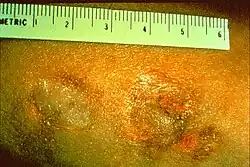

| Granulomas represent a focal chronic inflammatory reaction. These granulomas were produced by beryllium and are considered to be on a allergic basis. | |

Beryllium granulomas is a skin condition caused by granulomatous inflammation of the skin which may follow accident laceration, usually in the occupational setting.[1]: 46